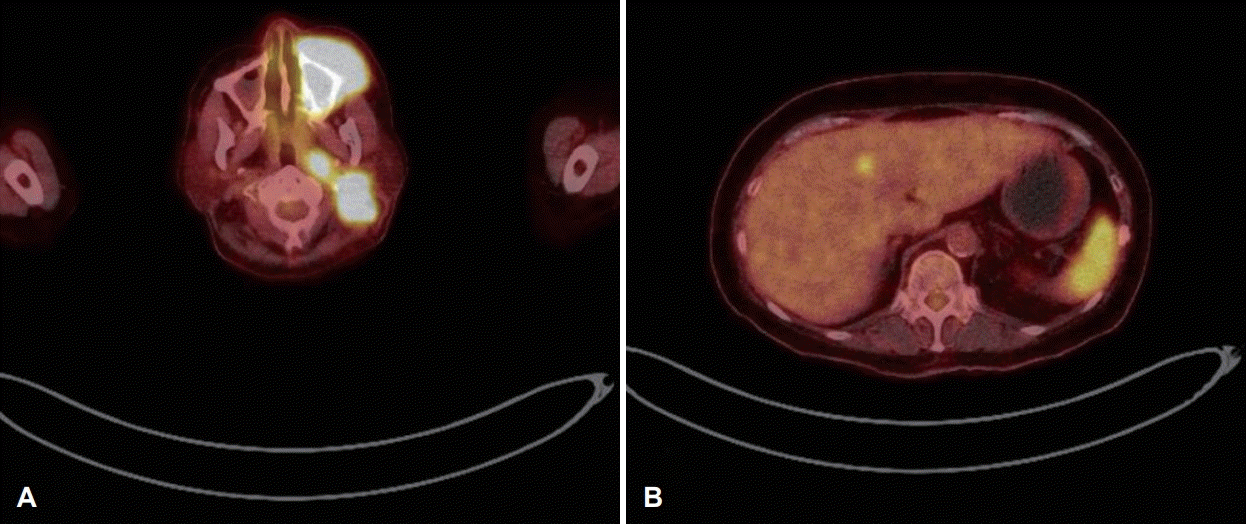

술 후 당일 시행한 조영 증강 경부 전산화단층촬영에서 좌측 상악동, 상악동 앞쪽 부위 및 협부 점막에 걸쳐 조영이 증강되는 5.5 cm 연조직 종괴가 관찰되었고(Fig. 4A), 좌측 측경부와 인두후부에 다수의 림프절 전이 소견이 관찰되었다(Fig. 4B). 조영 증강 부비동 자기공명영상촬영에서는 동일 부위에 T2 강조영상에서 중간 신호 강도를 보이고(Fig. 5A), T1에서 저신호 강도를 보이며, 조영제를 사용한 T1 강조영상에서 조영 증강되는 연조직 종괴를 확인하였다(Fig. 5B). 술 후 5일째 시행한 양전자방출단층촬영에서 좌측 상악동, 전상악동 부위, 협부 점막 및 좌측 경부 림프절(Fig. 6A)에 fluorodeoxyglucose 섭취 증가와 함께 간과 비장(Fig. 6B)의 전이 의심 소견이 보였다. 폐의 우상엽 부위에는 수술 당일 조영 증강 경부 전산화단층촬영에서 보이지 않고 새롭게 관찰되는, 염증성 결절 의심 소견이 있어 조영 증강 흉부 전산화단층촬영을 추가로 시행하였고, 양성 병변이나 전암성 병변배제 위해 3개월 뒤 추적 관찰을 권유받았다. 이에 최종 좌측 상악동에서 기원한 폐외소세포암(cT4aN2bM1)으로 진단되었다. 이후 환자가 원하여 항암 치료를 위해 타 병원으로 전원되었다.

Post-operative positron emission tomography-CT images. It shows hypermetabolic soft tissue mass on the left cheek with invasion of left maxillary sinus, pre-maxillary space, buccal region, and multiple metastatic lymph nodes in the left retropharyngeal space and level II (A). Focal area of increased FDG uptake in the S4 of the liver, and heterogeneously increased FDG uptake in the spleen are found (B). FDG: fluorodeoxyglucose.